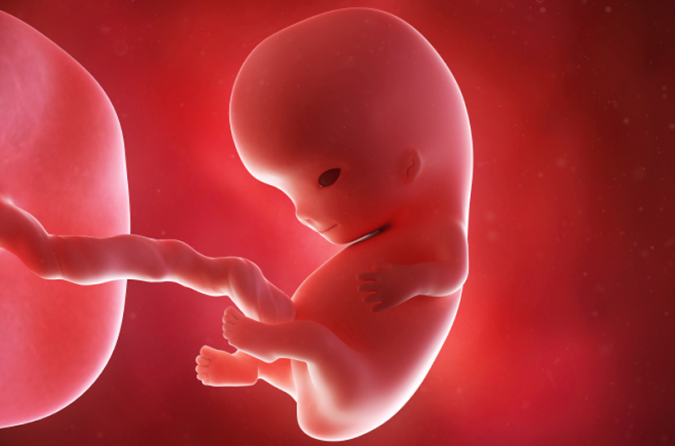

Baby Born Three Months Heads Home From Hospital January 12, 2026